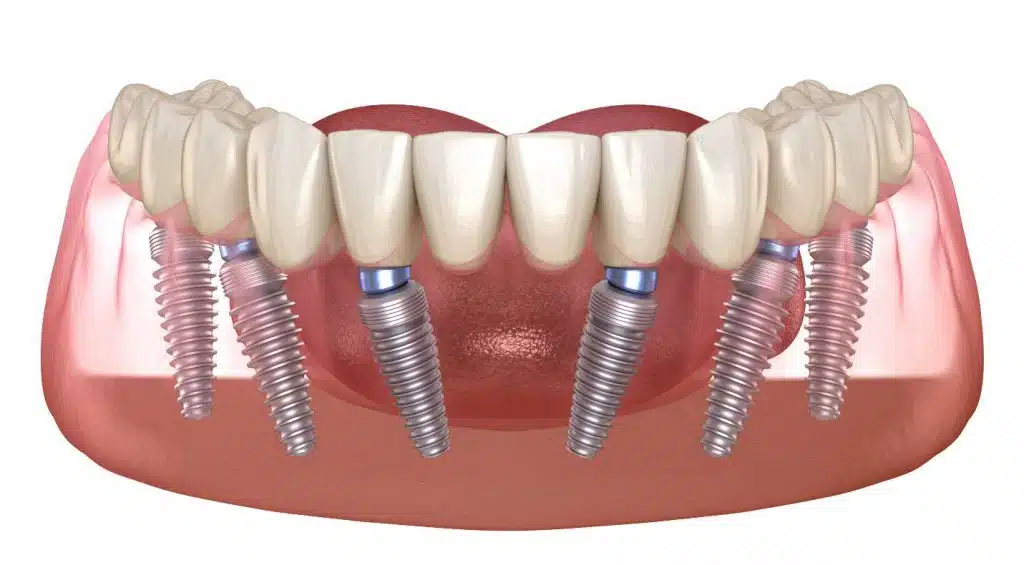

قدرت فک و لثه از جمله مواردی هستند که در تعداد ایمپلنت ها تاثیر می گذارد. عامل مهم دیگر کنار هم بودن یا نبودن جای خالی دندان هاست. اگر 5 جای خالی دندان در نقاط مختلف دهان باشند، برای آن ها 5 ایمپلنت نیاز است در حالی که اگر تعدادی از همین دندان ها نزدیک به هم باشند این عدد می تواند به 3 کاهش پیدا کند. اگر جای خالی دندان در فک بالایی باشد ایمپلنت های بیشتری مورد استفاده قرار می گیرد، چرا که فک بالا استخوان ضعیف تری دارد. کسانی که دندان قروچه دارند یا دارای عضلات مفصلی در فک هستند نیز، ایمپلنت های بیشتری نیاز خواهند داشت. نظر دقیق در این مورد را دندان پزشک پس از معاینه شما ارائه می کند. داشتن استخوان های بیشتر و متراکم تر باعث می شود ایمپلنت کمتری نیاز داشته باشید. متحرک یا ثابت بودن دندان ها نیز موضوعی است که بر تعداد ایمپلنت ها تاثیر می گذارد. دندان های متحرک تعداد ایمپلنت کمتری نسبت به دندان های ثابت نیاز دارند.

درباره روکش هم باید گفت، تعداد روکش ها دقیقا همان تعداد تعداد دندان هایی است که می خواهید ایمپلنت کنید. مثلا اگر چهار جای خالی دندان دارید حتی اگر کنار یکدیگر هم باشند به 4 روکش یا تاج دندان نیاز دارید.